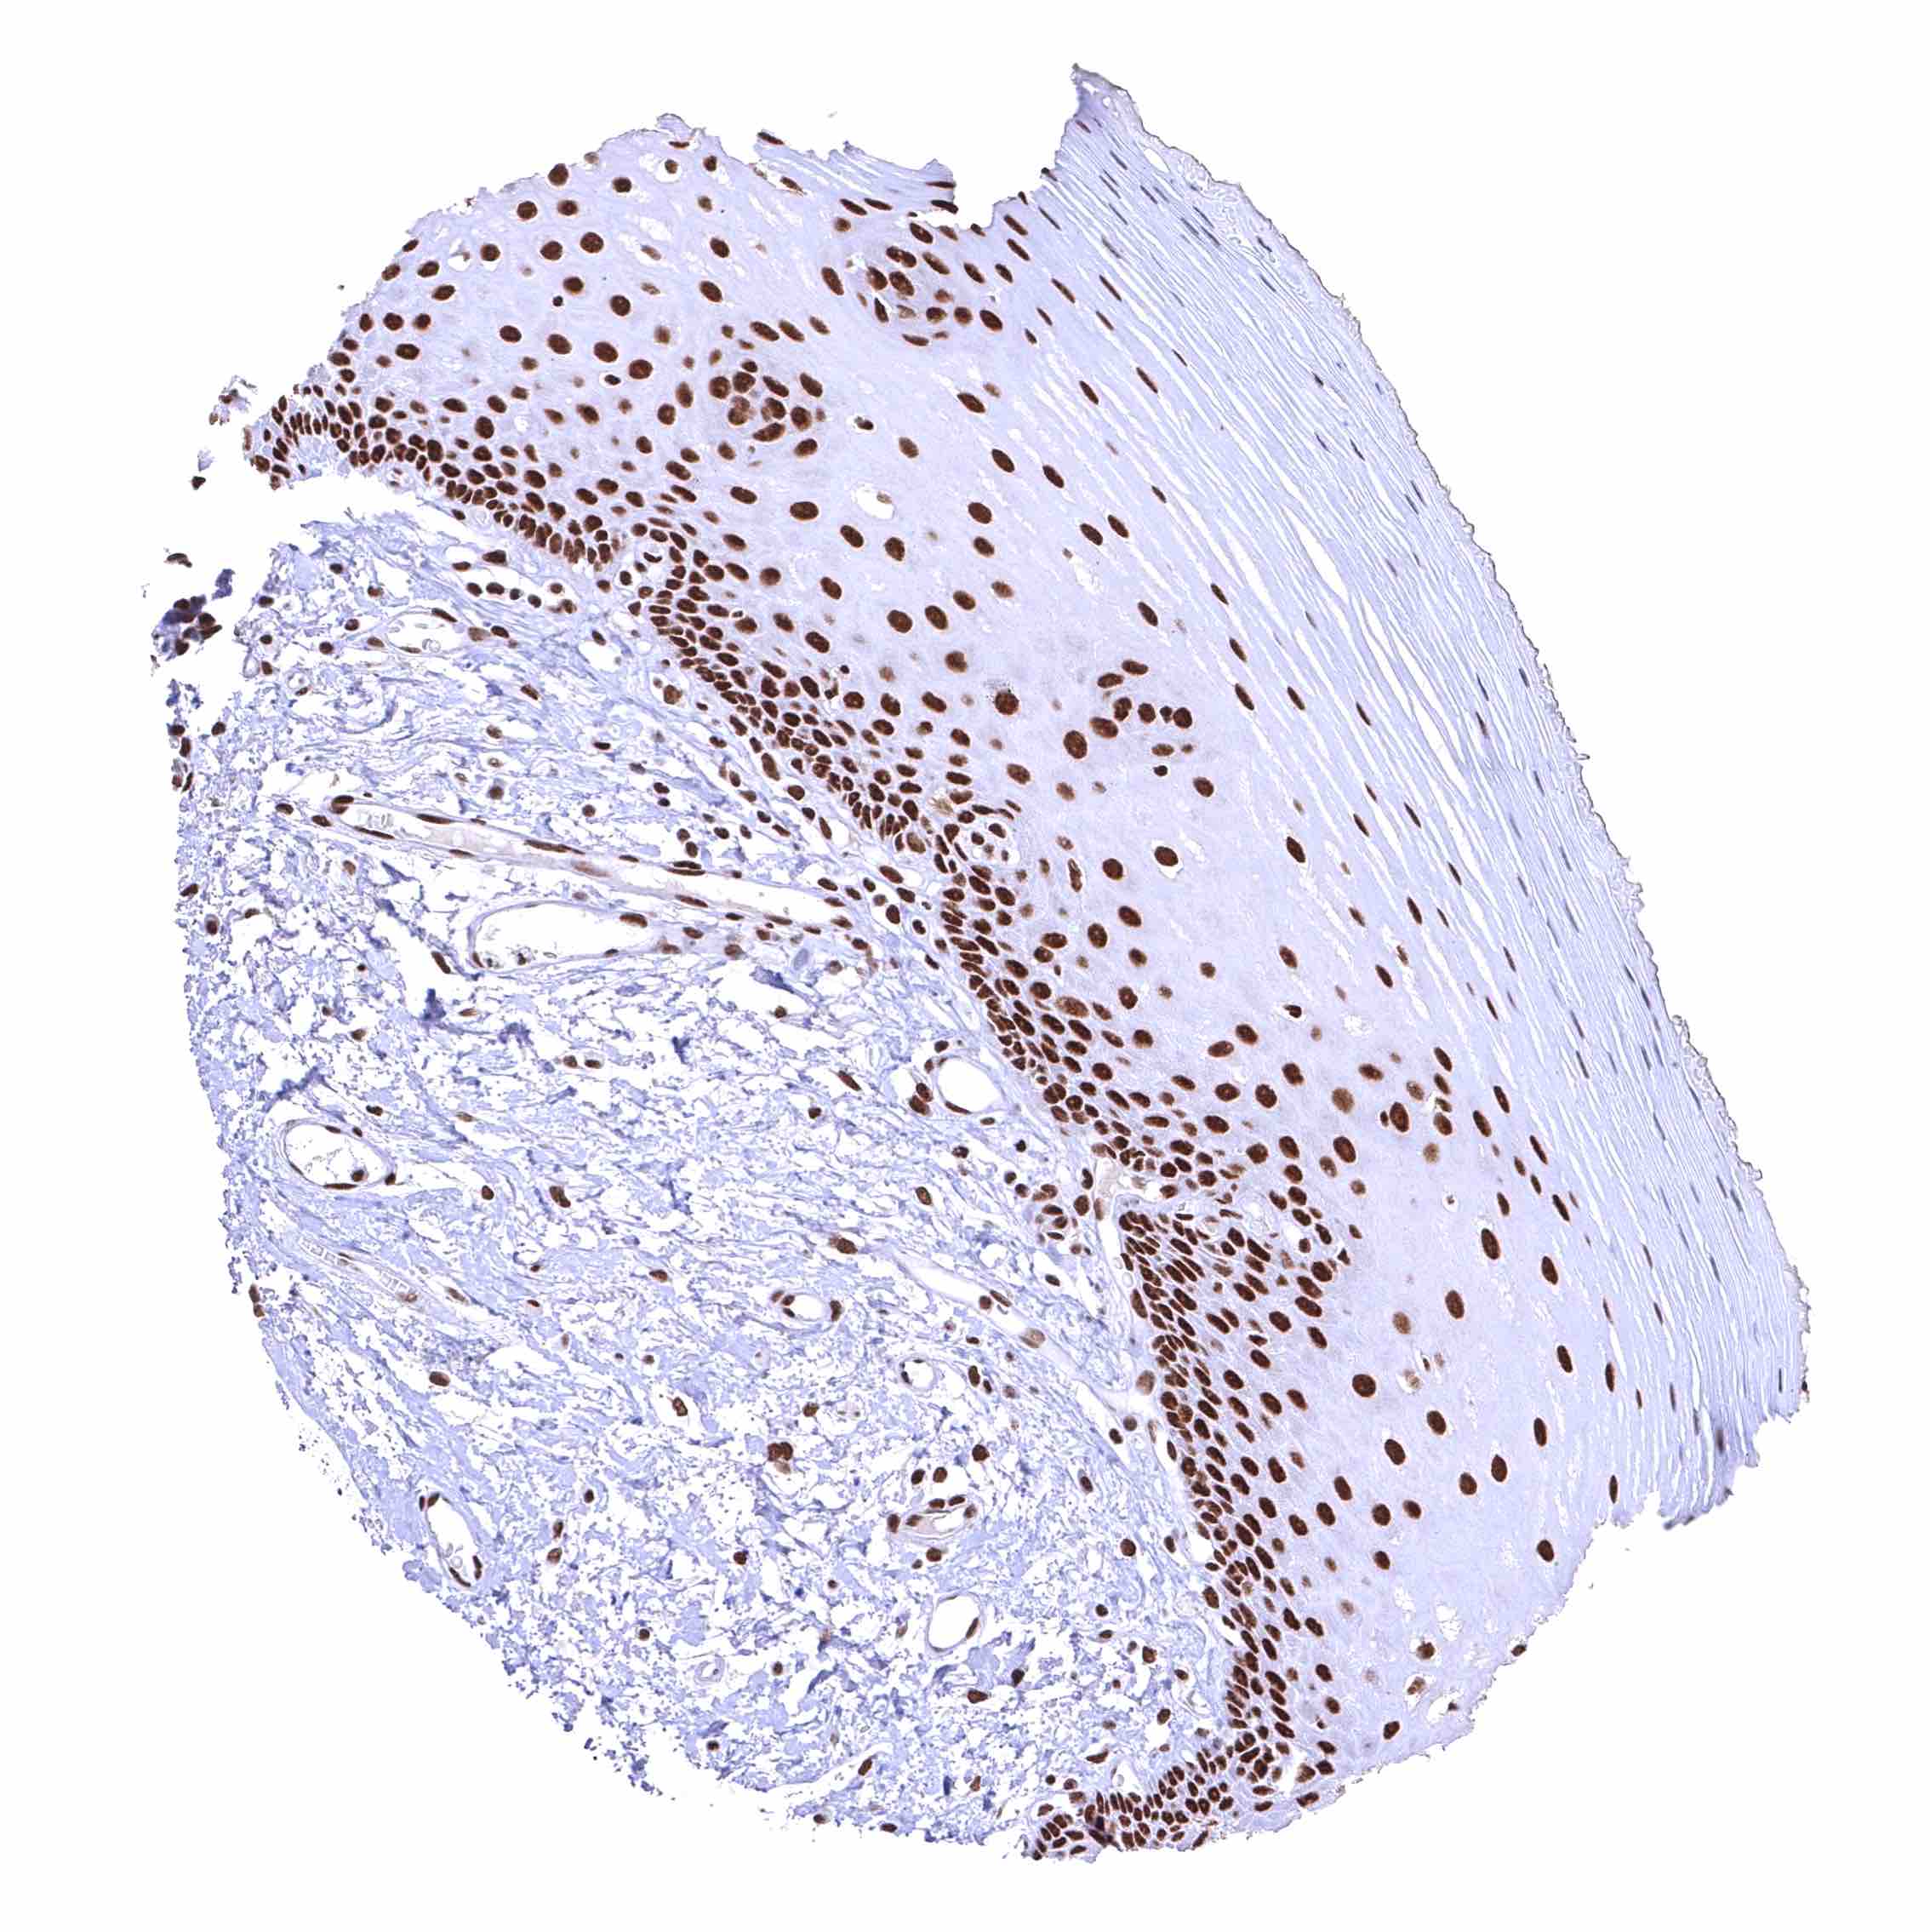

Uterus, ectocervix – Distinct nuclear BRD4 staining of squamous epithelial cells with a slight decrease of the staining intensity towards the most superficial cell layers.